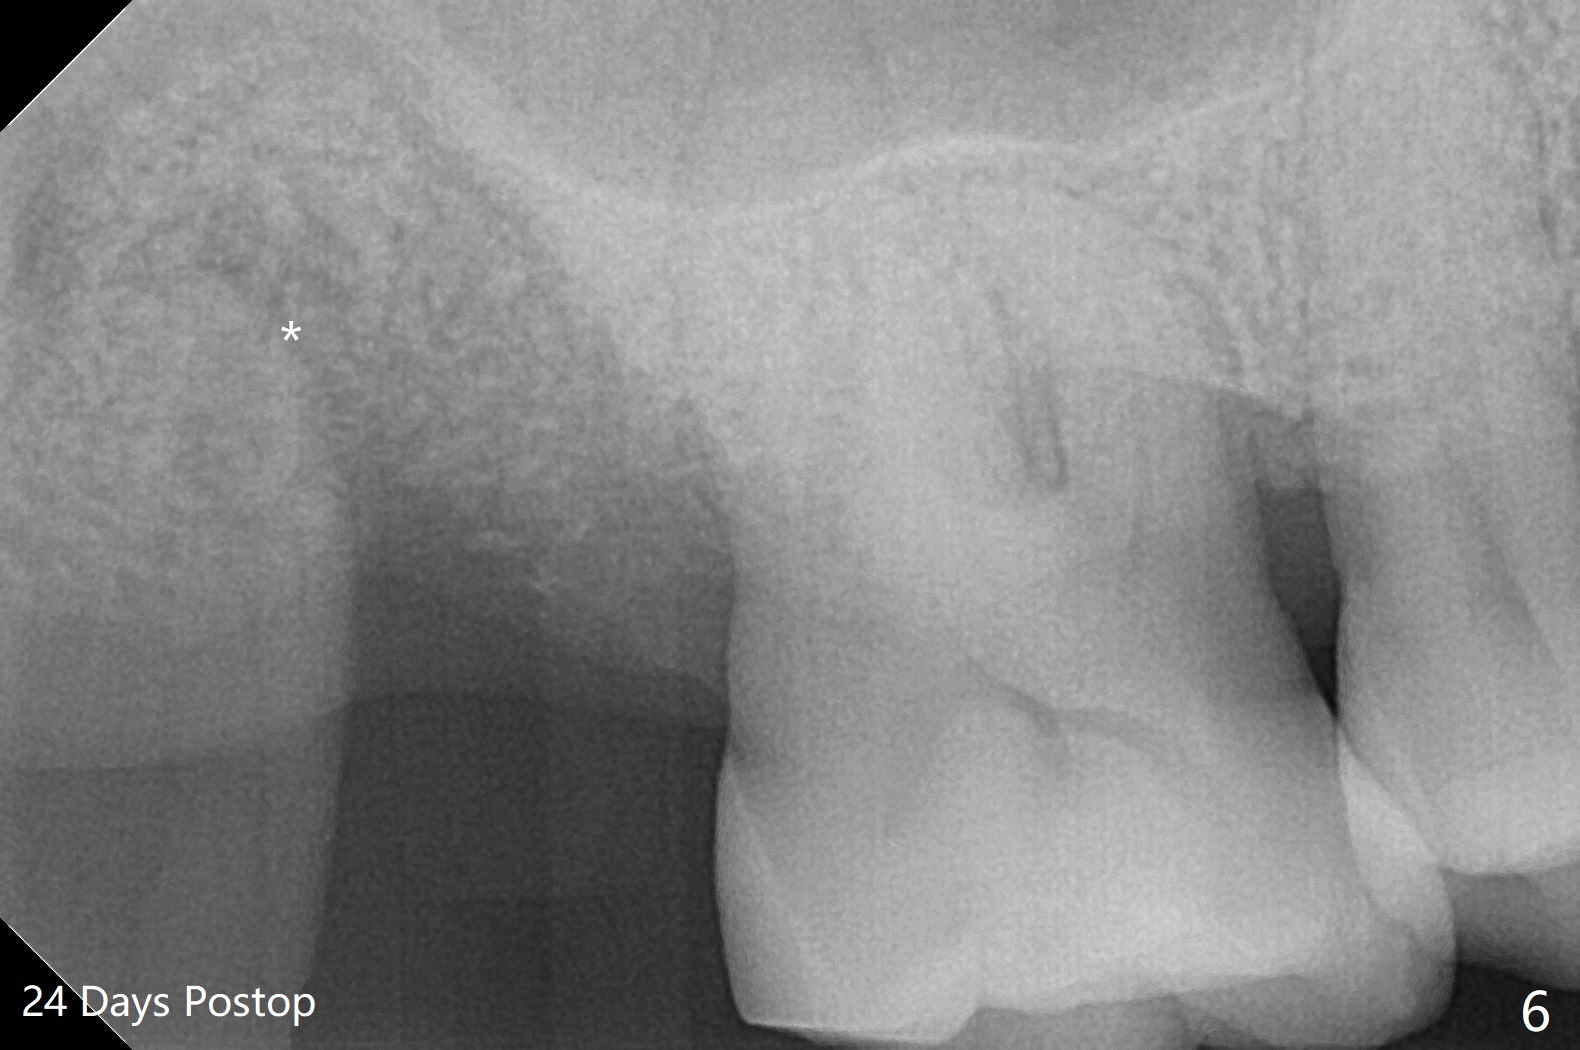

A 55-year-old woman requests extraction of the tooth #2 with pain and mobility a few weeks post SRP (Fig.1) and finally agrees with socket preservation (Fig.2,3 *). In fact the mesiobuccal root appears to have been fractured. She is a heavy bruxer (nuts). There is a large amount of granulation tissue in a large single socket. After suture fixation over Osteogen plug and allograft (*), a prefabricated band (B) and loop (L) are cemented in place. Periodontal dressing is applied mainly underneath the loop for wound protection and bone graft and membrane fixation. The central portion of the periodontal dressing remains in place over the socket opening 1 week postop (Fig.4). The removable distal portion of the loop dislodged 23 days postop. The free end of the fixed mesial portion of the loop is irritating; the patient returns the following day. After removal of the spacer, the socket appears to have healed (Fig.5). No bone graft has been lost (Fig.6 *, as compared to immediately postop (Fig.2,3)). Return to Upper Molar Immediate Implant, Trajectory Xin Wei, DDS, PhD, MS 1st edition 04/13/2019, last revision 01/06/2020